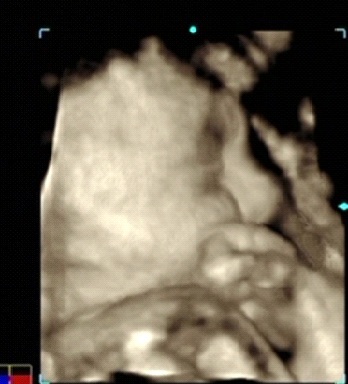

А вот и наше первое фото, мы здесь спим с серьезным лицом, уткнувшись лбом в матку, подпирая щеки кулачком)

Но самое главное, мы ходили с мужем на 3D узи! Правда нашему Ванечке узи не нравится, он все время личико прятал, грозил кулачком, и тер глазки) Но зато мы узнали, что малыш у нас уже прям слоненок, сказали, что по размерам идем с опережением на неделю.